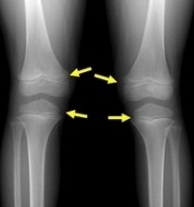

만약 당신이 당신의 아이의 키가 걱정된다면 당신은 지금부터 관심을 가질 필요가 있습니다. 하지만 중고등학교에 자녀를 둔 사람들은 성장판이 이미 닫혔다는 게 부질없다고 생각할 수도 있다. 질문이 있습니다! 성장판이 닫혀 있어도 키가 자랄 수 있을까요? 결론부터 말하자면, 그렇다.

그것은 또한 대부분의 사람들이 오해하는 것이다. 저희를 둘러보면 군대에서도 3~4cm 정도 자랐어요. 분명히 어떤 사람들은... 남자뿐만 아니라 여자도 20대 초반이다. 여러분은 아마 그가 키가 자라는 것을 본 적이 있을 거예요. 성장판이 닫혔을 때 키가 큰 이유는 다음과 같다. 어린 시절의 성장판은 스폰지처럼 부드럽다. 그러나 성장이 거의 끝날 때쯤 성장판은 점점 더 커지고 있다. 그것은 뼈처럼 단단해지고 있다. 그리고 이 과정을 통해 우리는 우리가 어떤 방식으로든 그것은 조금씩 커지고 있다.